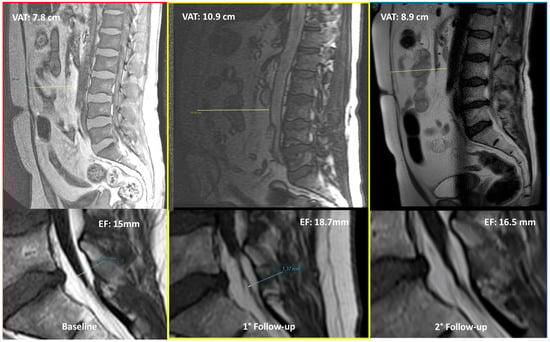

- VAT anterior–posterior max diameter at L3 level represented by the distance between the abdominal muscular fascia and the anterior wall of the abdominal aorta at the L3 vertebral level; MR-localizer sequences were used to achieve this aim (Figure 2, panel B).